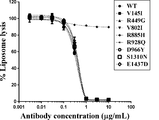

- Figure 19 illustrates inhibition of biological activity of wild type C5 (WT) and C5 variants (V145I, R449G, V802I, R885H, R928Q, D966Y, S1310N, and E1437D) by an anti-C5 antibody (eculizumab), as described in Example 8.4.

- Figure 20 illustrates inhibition of biological activity of wild type C5 (WT) and C5 variants (V145I, R449G, V802I, R885H, R928Q, D966Y, S1310N, and E1437D) by anti-C5 antibody (a 305 variant), as described in Example 8.4.